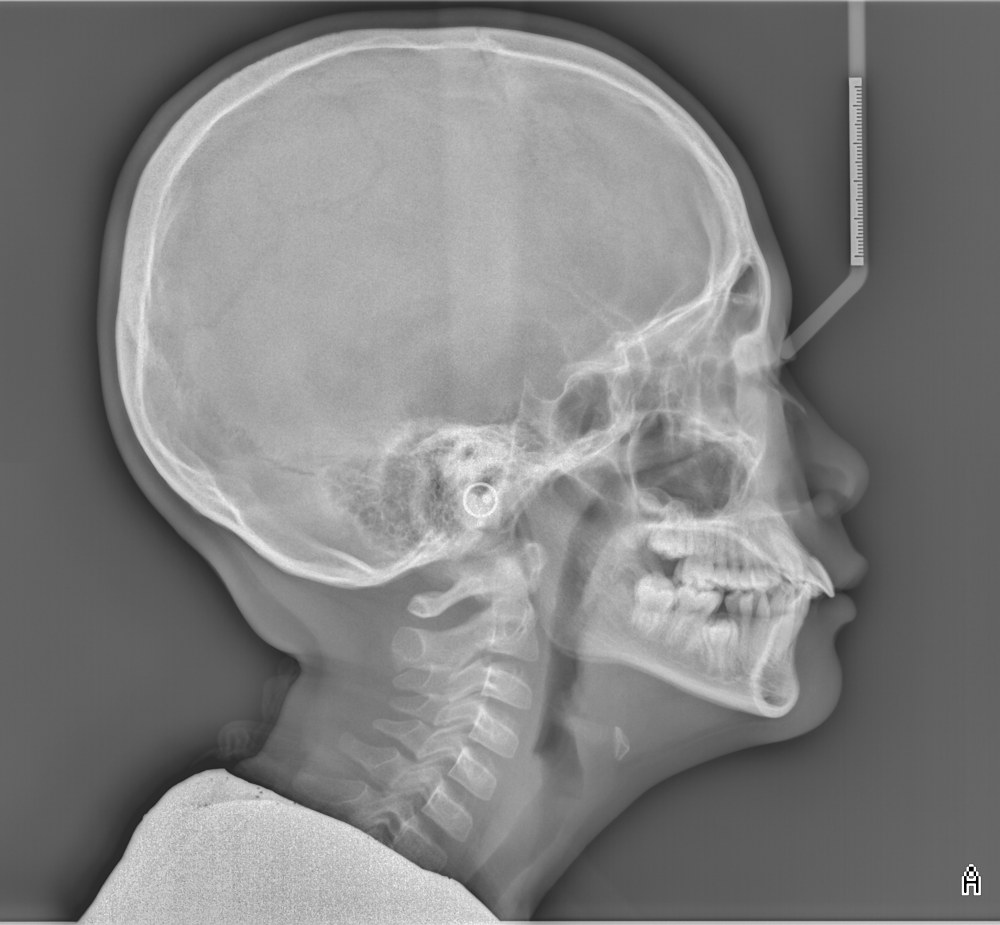

Upper Jawbone

Growth stop at ~8years old

Lower jaw growth → Improved airway and neck posture

Age

11 years old

Clinical observation

It is the under-developed lower jaw that is making the upper jaw appear protruded.

• The child developed a turtle neck posture to open up the airway.

Promote lower jaw growth (Angel Aligner’s A6 Mandibular Advancement Solution)

*side view focus on the lower jaw advancement

See the improvement in neck posture after the airway is opened up with lower jaw advancement.

Before

(Turtle neck)

After

(Good, upright posture)